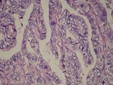

Hipertiroidizm Nedir?Hipertiroidizm, tiroid bezinin aşırı hormon üretmesi durumudur. Bu durum, gebelikte çeşitli komplikasyonlara yol açabilir. Hipertiroidizm, genellikle Graves hastalığı gibi otoimmün hastalıklardan kaynaklanır, ancak tiroidit veya tiroid nodülleri gibi diğer nedenler de olabilir. Gebelikte Hipertiroidizmin EtkileriGebelikte hipertiroidizm, hem anne hem de fetüs üzerinde olumsuz etkilere yol açabilir. Bunlar arasında: